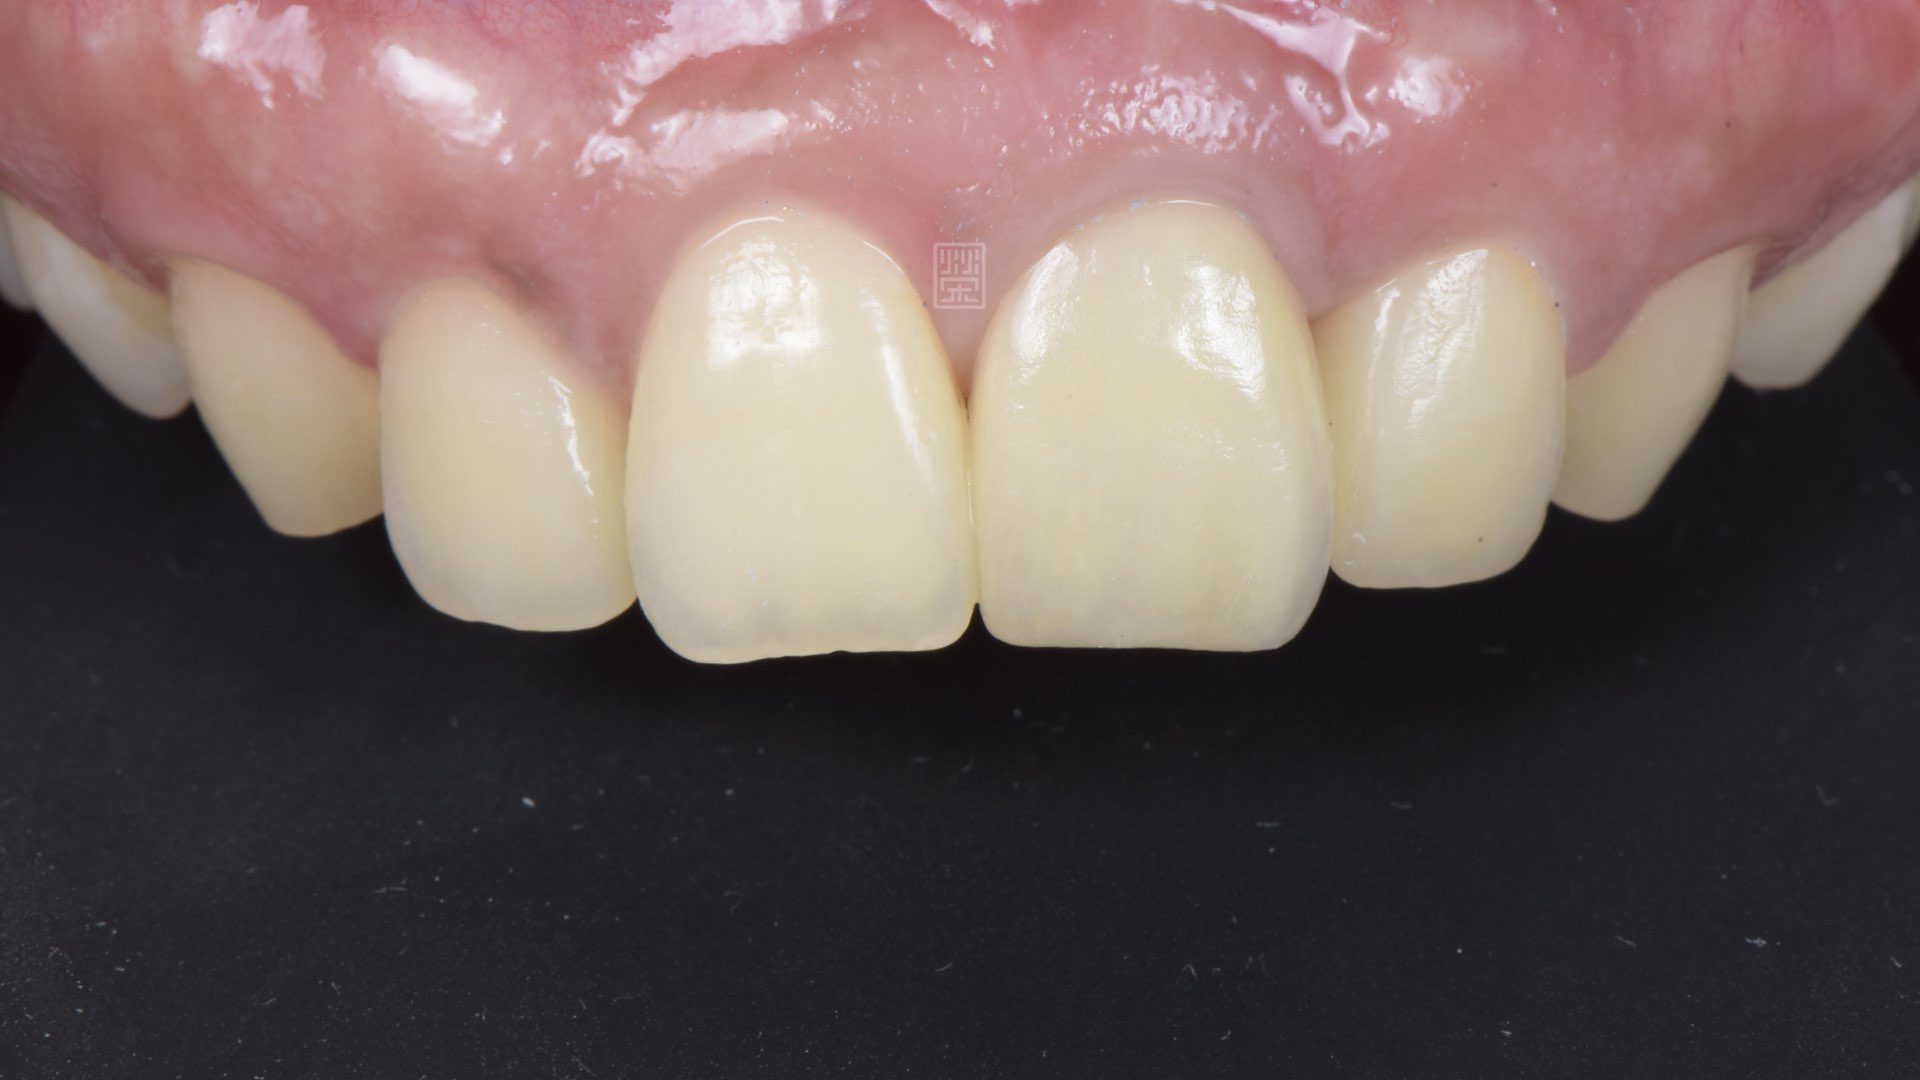

植牙全瓷冠

植牙完成